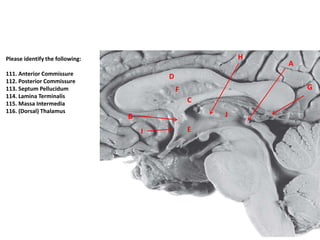

Please identify the following:

111. Anterior Commissure

112. Posterior Commissure

113. Septum Pellucidum

114. Lamina Terminalis

115. Massa Intermedia

116. (Dorsal) Thalamus

C

F

D

B

G

A

H

EI

J

111. B

112. A

113. F

114. I

115. H

116. J

Pineal gland is G